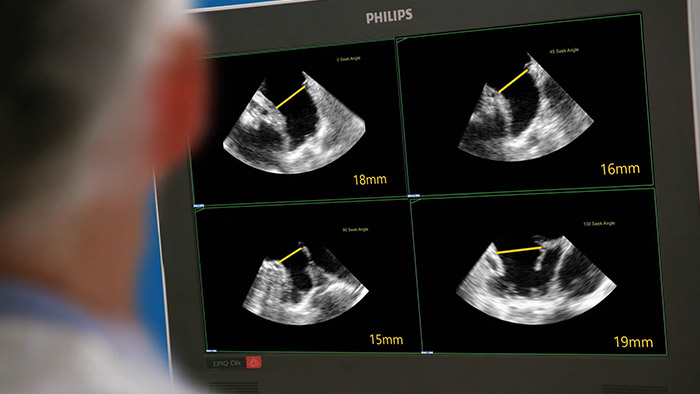

Evaluar la orejuela izquierda de forma rápida, fácil e intuitiva. La solución para la LAA de Philips en EPIQ CVxi.